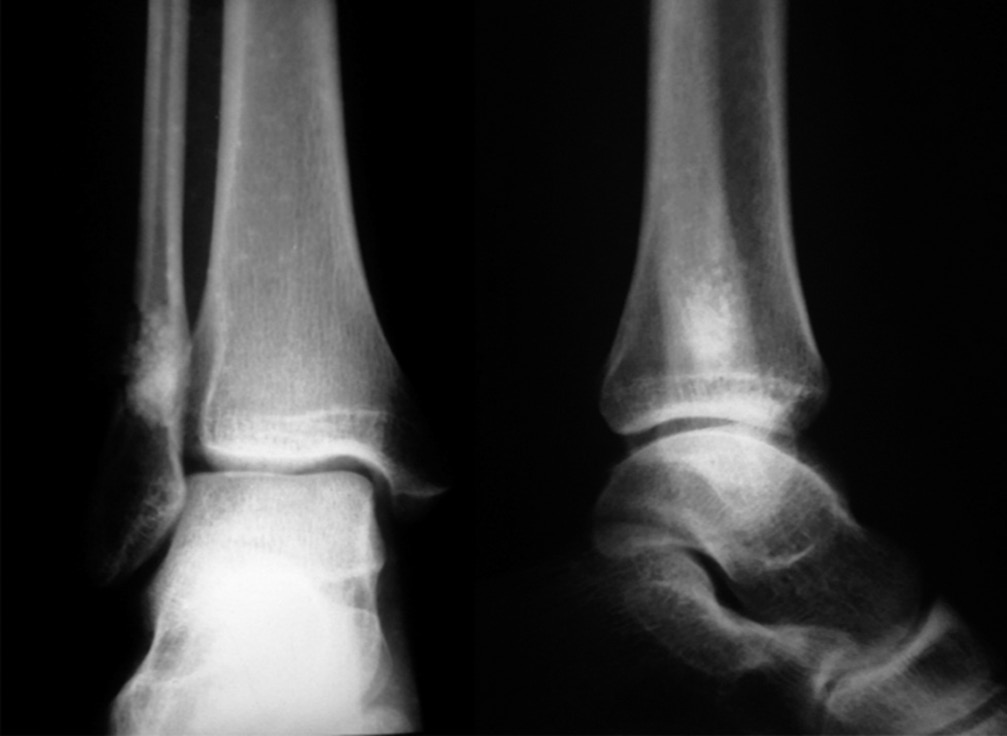

После получения травмы голеностопного сустава у 13-летней пациентки при рентгенологическом обследовании обнаружен очаг деструкции нижней трети правой малоберцовой кости овальной формы размером 1,9 × 0,8 см (30.11.2012) (рис. 1). Был рекомендован рентгенологический контроль через каждые 6 мес. Спустя год на снимке определялось увеличение размеров полости до 2,2 × 1,0 см. Пациентка жаловалась на непостоянный болевой синдром слабой выраженности (по визуальной аналоговой шкале (ВАШ) 2–3 балла), усиливающийся при физических нагрузках (по ВАШ до 5–6 баллов).

Рис. 1. Рентгенограмма. В проекции нижней трети правой малоберцовой кости кистозное образование овальной формы с четкими, ровными контурами, размером 1,9 × 0,8 см, кортикальный слой на уровне образования истончен